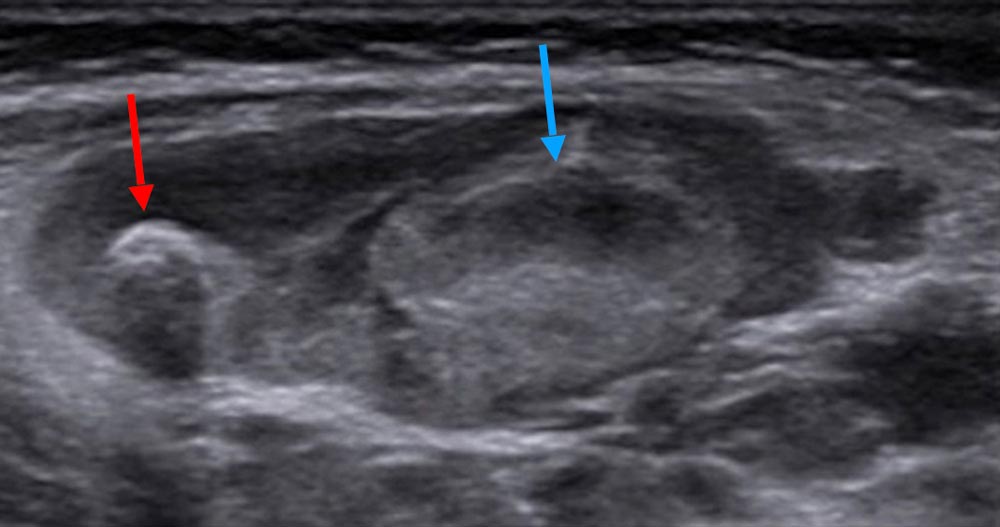

If imaging is ever necessary, sonography is the first choice. Thrombophlebitis is easily visualized within the anechoic venous malformation components as echogenic, non-compressible circumscribed foci.

On sonography, a normal vein or venous malformation is soft and readily compressible with the transducer. The non-clotted blood is virtually anechoic (black), and slow blood flow is detectable on color-coded duplex sonography.

As the blood clot matures with time, it becomes more echogenic sonographically, making it easy to distinguish from anechoic blood. Often starting at the edge, i.e., at the vessel wall, there is a slow recanalization of the involved vessel. This is visible as anechoic fluid around the echogenic thrombus.